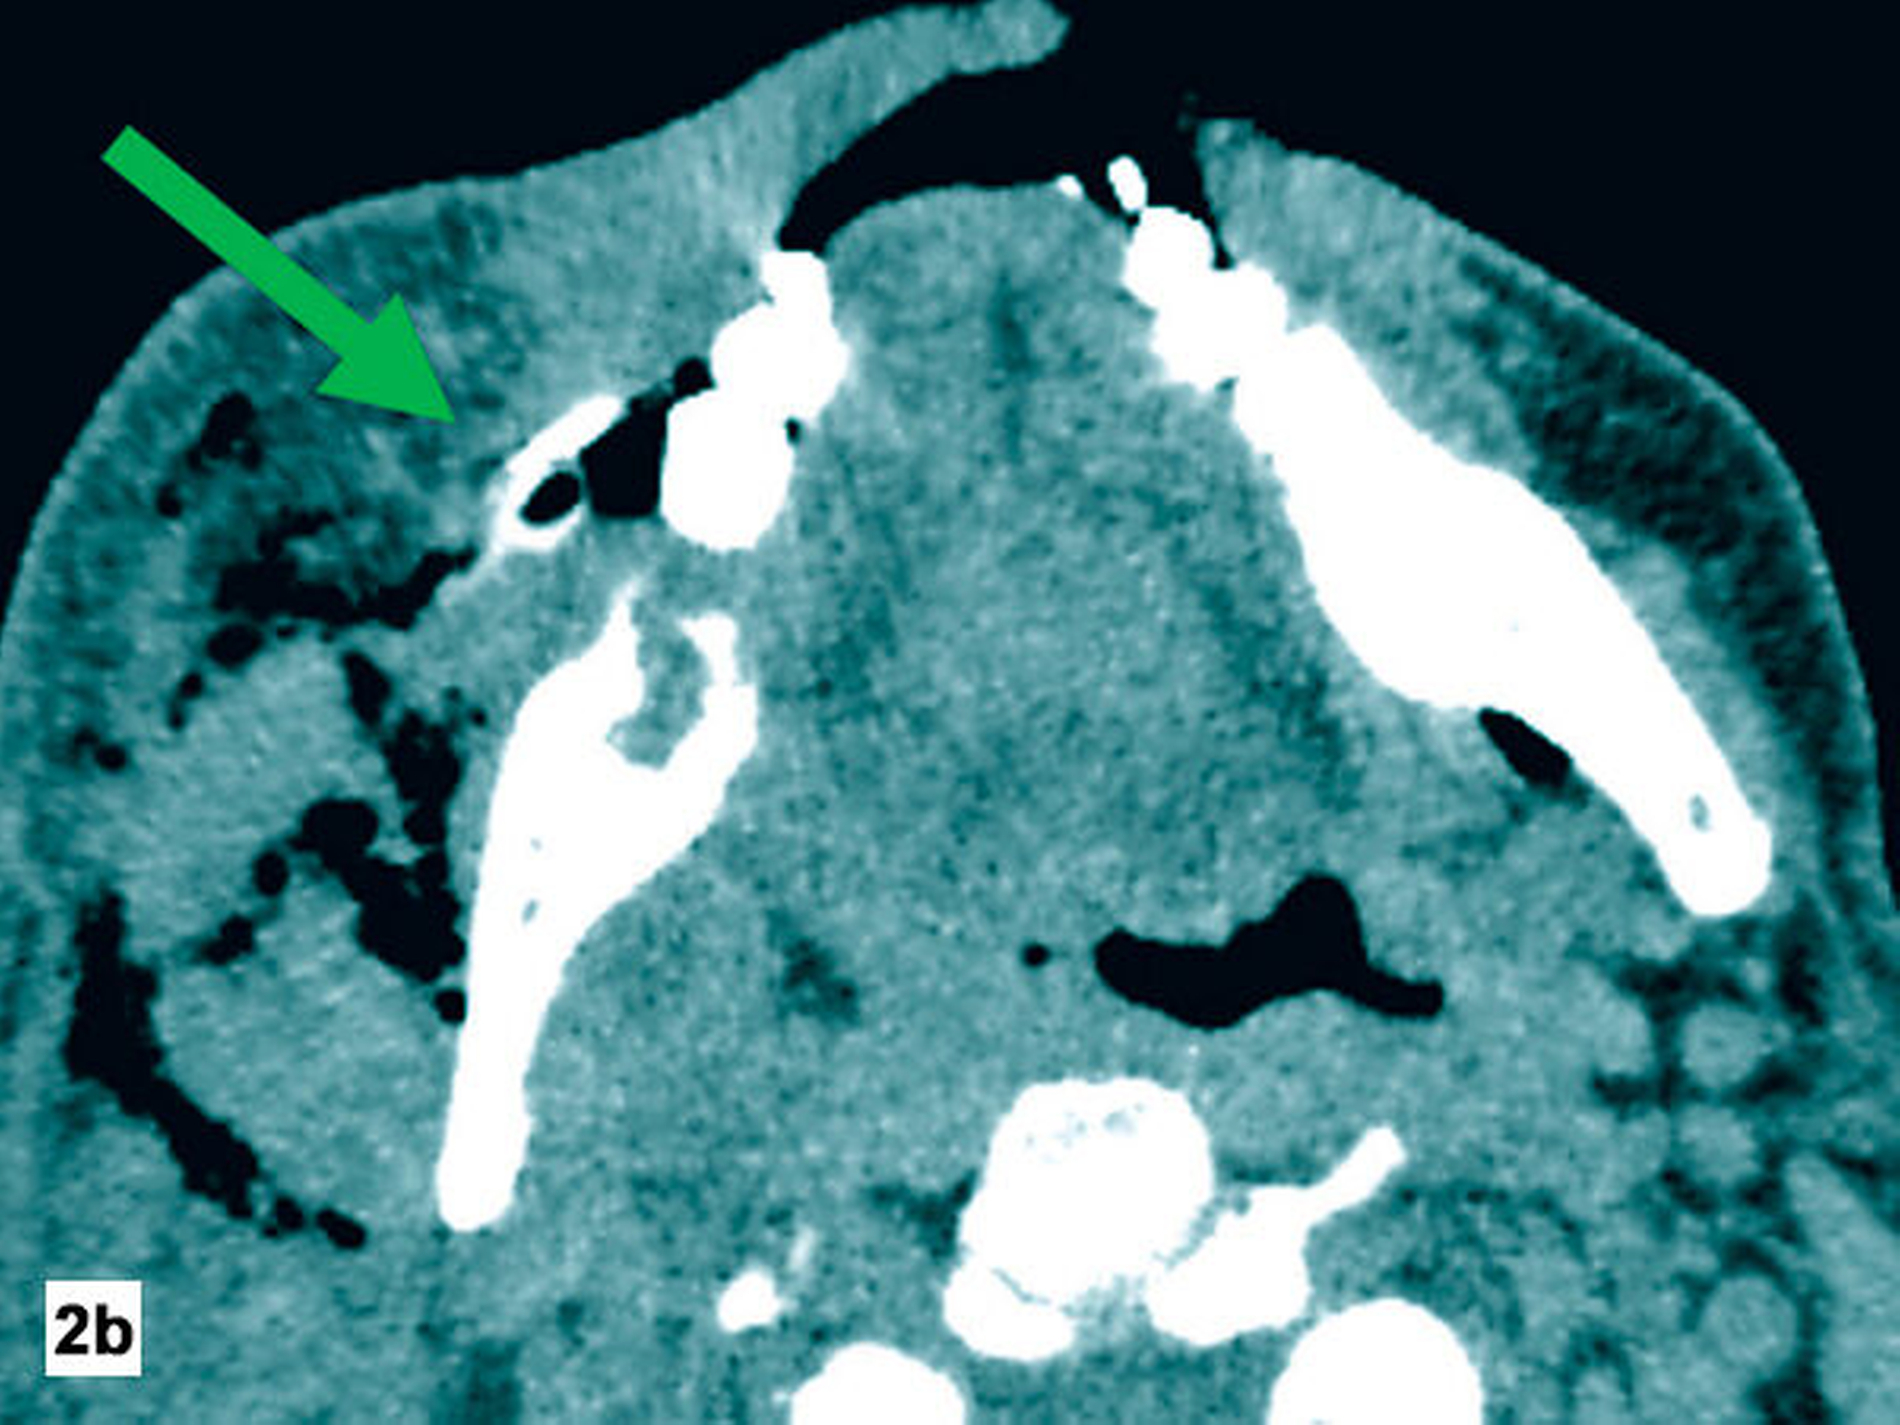

Am Folgetag zeigte der Patient eine zunehmende Verschlechterung und eine progrediente Schwellung der Halsregion mit beginnender Luftnot. Zur erweiterten Diagnostik wurde eine Computertomografie (CT) der Kopf-Hals-Region durchgeführt (Abbildung 2). Hier zeigten sich ein Flüssigkeitsverhalt submandibulär rechts trotz loco typico einliegender Drainage sowie Gewebseinschmelzungen und Gasblasen entlang des rechtsseitig-zervikalen und temporalen Faszienverlaufs.

Zur Diagnostik wird eine Schnittbilddiagnostik, in der Regel eine Computertomografie, empfohlen. Hierbei zeigen sich, wie im hier vorliegenden Fall, typischerweise Luftansammlungen und Gewebseinschmelzungen. Die Abgrenzung von Kutis und Subkutis ist regelhaft nicht mehr möglich [Kämmerer et al., 2017]. Das Vorliegen einer nekrotisierenden Fasziitis kann zusätzlich mit dem „Laboratory Risk Indicator for Necrotizing Fasciitis Score“ (LRINF) eingeschätzt werden, der positiv-prädiktive Wert wird in fortgeschrittenen Stadien mit 92 Prozent angegeben [Wong et al., 2004].